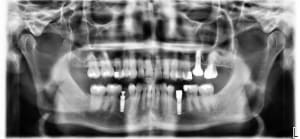

10-07-2025 Panoramique Fin.JPG